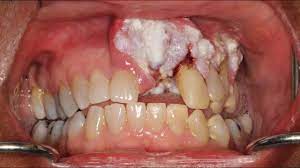

What Does Mouth Cancer Look Like : Avoid Mouth Cancer In 2021 Alexandria Smiles - It's important to be aware of the symptoms of mouth cancer so you can contact your gp or dentist if you notice anything abnormal.. Cancer is defined as the uncontrollable growth of cells that invade and cause damage to surrounding tissue. After the surgeon locates the tumor, a laser is used to divide the tumor into sections. Gum cancers may start out looking like a bump or a sore that does not heal. Oral cancer appears as a growth or sore in the mouth that does not go away. Oral cancer can affect the mouth including the gums, lips, tongue, mouth's roof, and floor and the inner cheeks.

A deep fissure containing a small ulcer erosion of the mucosa resulting in a raw superficial area Canker sores can be found anywhere in the mouth from the cheek, inner lip, on and under the tongue, and even in the throat. Health scotland and glasgow dental hospital learn more about reducing the risk of oral cancer The following are some characteristic features of how mouth cancers look for people wondering what does mouth cancer look like. A white or red patch inside your mouth or on your lips may.

Cancer of the floor of mouth often looks like an ulcer and is painless. Mouth cancer usually presents with distinctive symptoms and features, such as red or white patches in the mouth, changes in oral tissue, or difficulty chewing or swallowing. These are the basic stages of mouth cancer: With no determined cause, mouth cancer in dogs has left even subject matter experts baffled. Some symptoms of mouth cancer are noticeable, that makes it possible to detect mouth cancer in its early stages. Canker sores can be found anywhere in the mouth from the cheek, inner lip, on and under the tongue, and even in the throat. According to the american cancer society, a red patch on your lip that becomes crusty, itchy, or bleeds is a warning sign. The appearance of feline oral cancer can vary significantly, depending on the type of cancer and how far advanced the cancer is. Patches on the lining of the mouth or tongue, usually red or red and white bleeding, pain, or numbness in the mouth mouth ulcers or sores that do not heal It's important to be aware of the symptoms of mouth cancer so you can contact your gp or dentist if you notice anything abnormal. The most common types of oral cancers in dogs are melanoma, squamous cell carcinoma and fibrosarcoma. Some of the signs are similar, including bleeding gums. Common signs or symptoms of lip cancer include visible irregularities in the skin on the lower lip.

What some oral (mouth) cancers look like these photographs are not meant to scare you. They are typically round with a depressed center and may appear to be white, grey or yellow. Health scotland and glasgow dental hospital learn more about reducing the risk of oral cancer According to the american cancer society, a red patch on your lip that becomes crusty, itchy, or bleeds is a warning sign. Changes in the look and feel of the tissue on the floor of the mouth, such as a lump or a sore that doesn't heal, are often the first signs of floor of the mouth cancer.

After the surgeon locates the tumor, a laser is used to divide the tumor into sections. It describes abnormal cells in the lining of the lips or oral cavity, which have the potential to become cancer. Canker sores can be found anywhere in the mouth from the cheek, inner lip, on and under the tongue, and even in the throat. Picture of squamous cell carcinoma of the cheek Health scotland and glasgow dental hospital learn more about reducing the risk of oral cancer

5 Ways To Self Examine For Oral Cancer Ocoee Oral Surgery from www.ocoeeoralsurgery.com According to the american cancer society, a red patch on your lip that becomes crusty, itchy, or bleeds is a warning sign. As with any disease of its kind, keeping informed can help you decipher what to do should a tumor linger in your dog's mouth, and even prevent it from. Hypopharyngeal cancer (laryngopharyngeal cancer) begins in the hypopharynx (laryngopharynx) — the lower part of your throat, just above your esophagus and windpipe. Mouth cancer on your gums can sometimes be mistaken for gingivitis, a common gum inflammation. The outer rim of the canker sore is typically red. Here are some symptoms you can look for, options for treatment and the life expectancy for dogs with mouth cancer. An ulcer that starts bleeding when touched, having rolled edges and a crater in the centre. The following are some characteristic features of how mouth cancers look for people wondering what does mouth cancer look like.

The following are some characteristic features of how mouth cancers look for people wondering what does mouth cancer look like.

An ulcer that starts bleeding when touched, having rolled edges and a crater in the centre. Some symptoms of mouth cancer are noticeable, that makes it possible to detect mouth cancer in its early stages. A deep fissure containing a small ulcer erosion of the mucosa resulting in a raw superficial area Here are some symptoms you can look for, options for treatment and the life expectancy for dogs with mouth cancer. As with any disease of its kind, keeping informed can help you decipher what to do should a tumor linger in your dog's mouth, and even prevent it from. Picture of squamous cell carcinoma of the cheek Common signs or symptoms of lip cancer include visible irregularities in the skin on the lower lip. Hypopharyngeal cancer (laryngopharyngeal cancer) begins in the hypopharynx (laryngopharynx) — the lower part of your throat, just above your esophagus and windpipe. These are the basic stages of mouth cancer: Cancer is defined as the uncontrollable growth of cells that invade and cause damage to surrounding tissue. Health scotland and glasgow dental hospital learn more about reducing the risk of oral cancer The surgeon looks at the soft palate, through the mouth and nose, using a special instrument. How common is mouth cancer in cats?